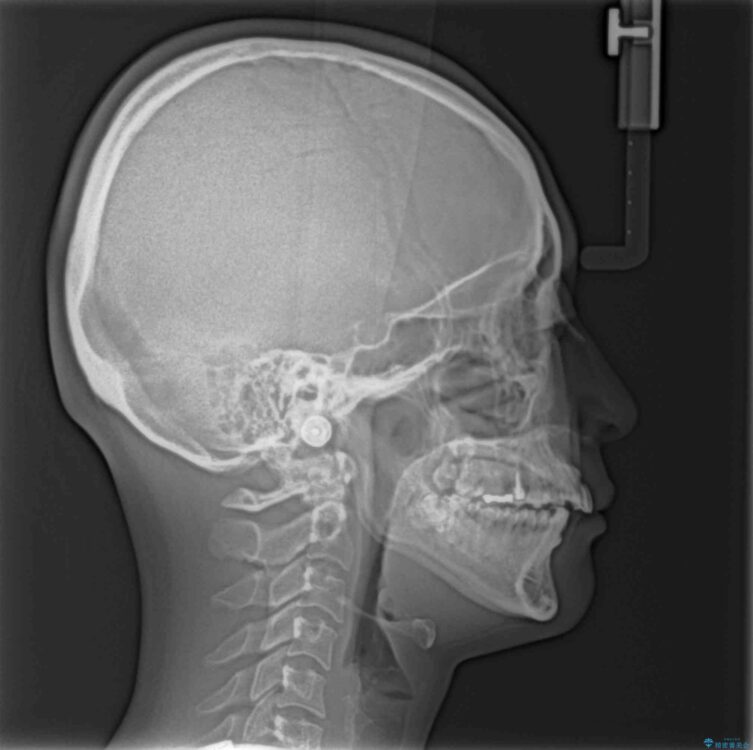

飛び出た上の前歯を気にして来院された患者様です。

奥歯の咬み合わせは、上顎歯列が理想的な一よりも数mm前方にある状態でした。

なるべく早めに治療を終えたいとのことで、補助装置を用いて上顎臼歯を後方に移動させ、同時にワイヤー装置にて整えることとしました。